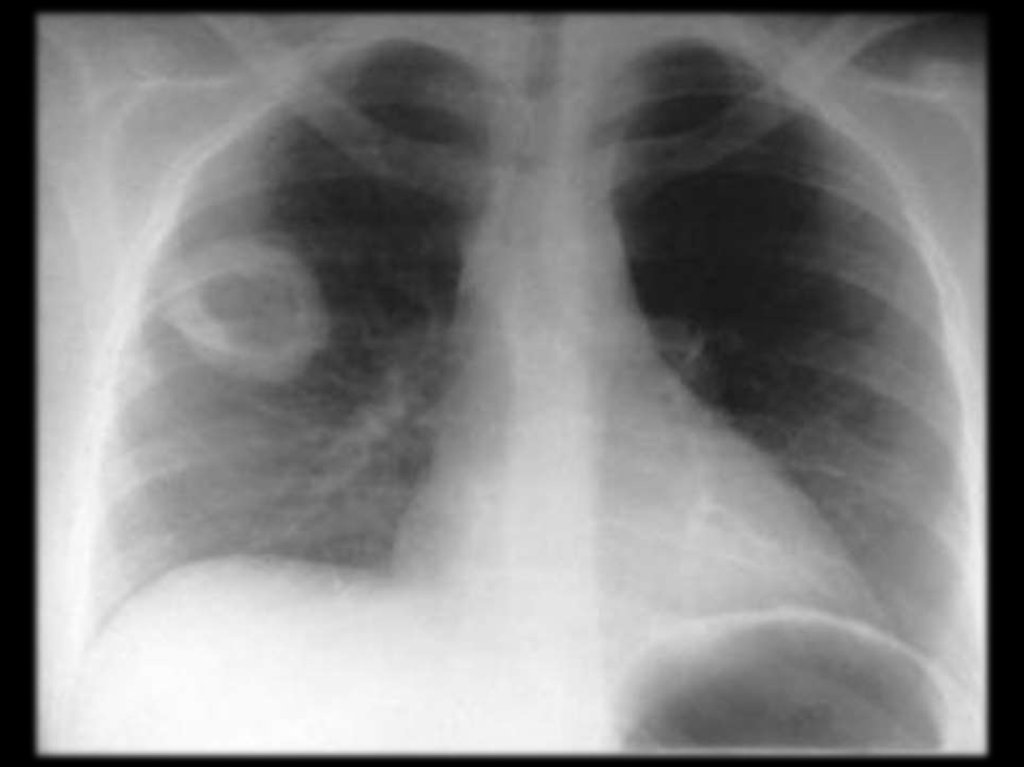

Поражение

лёгких

встречается

практически у всех больных: кашель,

иногда

надсадный,

боль

в

груди,

одышка, кровохарканье.

Аускультативная картина весьма скудная.

R-признаки

лёгочной

патологии

разнообразны:

узлы,

инфильтраты,

образование

полостей,

очаговые

ателектазы, экссудативный плеврит.